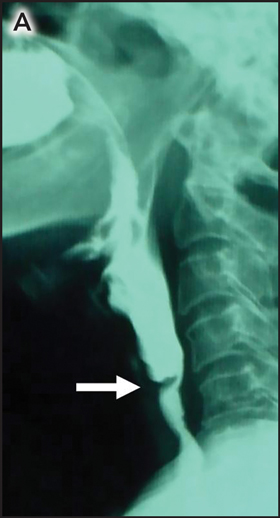

A 45-year-old woman presented with a 6-month history of dysphagia. Pallor and koilonychia were present on examination. Laboratory tests revealed microcytic hypochromic anaemia (haemoglobin, 59 g/L; mean cell volume, 65 fL), with decreased iron stores (on serum iron studies and bone marrow examination). Barium swallow (Figure A) and oesophagoscopy (Figure B) revealed an upper oesophageal web, which was fractured using Savary–Gilliard dilators. A diagnosis of Plummer–Vinson syndrome (oesophageal web, dysphagia and sideropenic anaemia) was made. As further investigations gave negative results (oesophagoduodenoscopy, colonoscopy, duodenal biopsy, measurement of anti-tissue transglutaminase antibodies, and stool examination for occult blood, ova and cysts), we attributed the iron deficiency to inadequate iron intake. This syndrome is associated with upper alimentary tract cancer, and surveillance endoscopy is recommended.